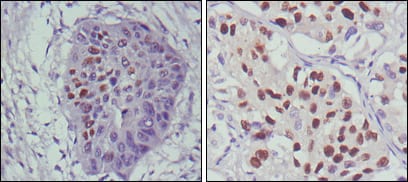

分类: 科研抗体货号: 20341别名: CD28LG; LAB7; B7.1应用: IHC,IF反应种属: Human